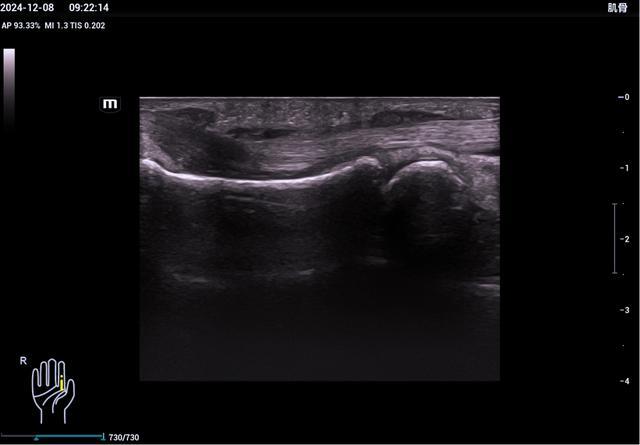

7、手部超声检查

三角纤维软骨复合体TFCC损伤、腱鞘炎、指伸肌腱损伤、掌腱膜挛缩、腱鞘巨细胞瘤、腱鞘囊肿、血管球瘤、腱帽损伤并伸肌腱滑脱、钙化性关节周围炎、手异物等。